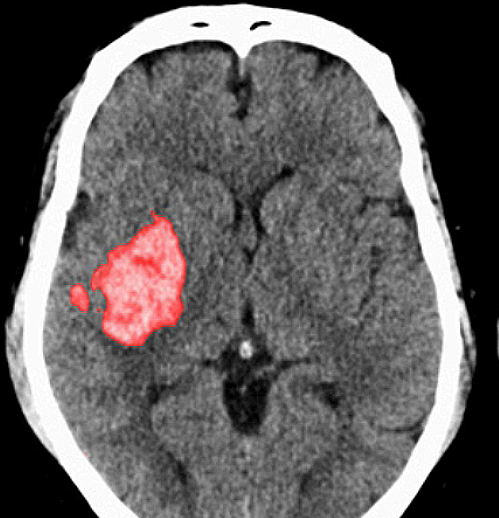

뇌졸중은 뇌 일부분에 혈액을 공급하는 혈관이 막히거나 터지면서 뇌가 손상돼 신경학적 이상이 나타나는 병입니다. 밤과 낮 그리고 실내외 온도 차가 계절에는 혈압 상승과 혈관 과부하로 심뇌혈관 질환 발병 우려가 매우 높습니다.

뇌에 혈액을 공급하는 혈관이 막히게 되면 뇌의 일부가 손상되는 ‘뇌경색 증상’, 뇌혈관이 터져 주변 뇌가 손상되는 ‘뇌출혈 증상’이 있습니다. 두 질병 모두 사망에 이르거나 뇌손상으로 인한 후유증이나 신체장애를 남길 수 있는 위험한 질환입니다.